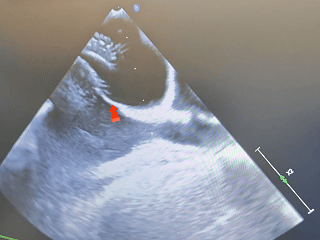

成型良好

第一个封堵器形态良好

封堵器植入后,测量小缺损发现略微缩小,缺损约5mm,

随即选择可降解BDASD-Ⅰ10封堵器封堵5mm缺损

双封堵器释放后超声